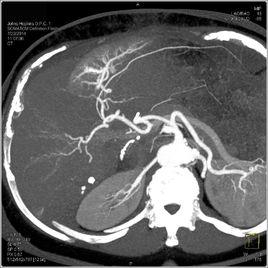

(二)CT檢查:

CT能清晰地顯示肝內鈣化灶的部位、大小、形態及伴隨病變,增強掃描還可確定B超難以顯示的局限性輕度膽管擴張和肝萎縮,並除外其它病變。